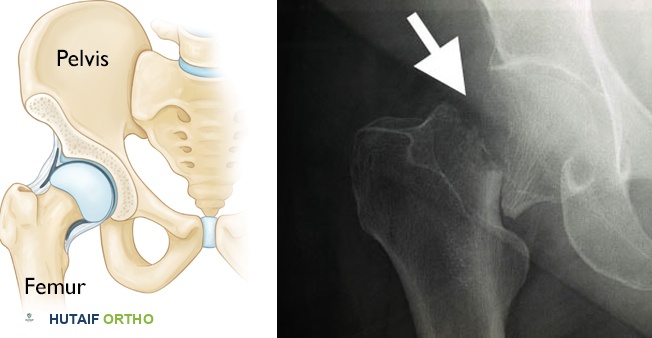

مفصل الورك هو أحد أكبر وأهم المفاصل في جسم الإنسان، ويلعب دورًا حيويًا في الحركة، المشي، والقدرة على تحمل وزن الجسم. يتكون هذا المفصل الكروي الحقي من التقاء رأس عظم الفخذ (الجزء العلوي الكروي من عظم الفخذ) مع التجويف الحقي (تجويف على شكل كوب في عظم الحوض). يسمح هذا التركيب المعقد بحركة واسعة النطاق في اتجاهات متعددة، مما يمنح الجسم مرونة كبيرة.

تُحيط بالمفصل مجموعة قوية من الأربطة والعضلات والأوتار التي توفر الاستقرار والدعم، وتسمح بالحركة السلسة. عندما نتحدث عن "كسر الورك"، فإننا نشير عادةً إلى كسر يحدث في الجزء العلوي من عظم الفخذ، وتحديدًا في المناطق التالية:

- عنق الفخذ (Femoral Neck): المنطقة الضيقة التي تربط رأس الفخذ بالجسم الرئيسي للعظم. هذه الكسور غالبًا ما تكون داخل كبسولة المفصل.

- المنطقة المدورية (Intertrochanteric Region): المنطقة الواقعة بين المدور الكبير والمدور الصغير لعظم الفخذ، وهما نتوءان عظميان كبيران يقعان أسفل عنق الفخذ مباشرة. هذه الكسور تكون خارج كبسولة المفصل.

- المنطقة تحت المدورية (Subtrochanteric Region): المنطقة الواقعة أسفل المدورين مباشرة، وهي الجزء العلوي من جسم عظم الفخذ.

- الأشعة السينية (X-rays): تُعد الأشعة السينية هي الفحص الأول والأكثر شيوعًا لتشخيص كسور الورك. يمكنها عادةً تأكيد وجود الكسر وموقعه ونوعه.

تحدث كسور الورك في الجزء العلوي من عظم الفخذ. تُظهر صورة الأشعة السينية على اليمين كسرًا في الورك.- التصوير بالرنين المغناطيسي (MRI): في بعض الحالات، قد لا تظهر كسور صغيرة أو كسور شعرية بوضوح في الأشعة السينية، خاصةً إذا كانت العظام ضعيفة جدًا. في هذه الحالات، قد يطلب الطبيب إجراء تصوير بالرنين المغناطيسي، والذي يوفر صورًا مفصلة للعظام والأنسجة الرخوة ويمكنه الكشف عن الكسور الخفية.